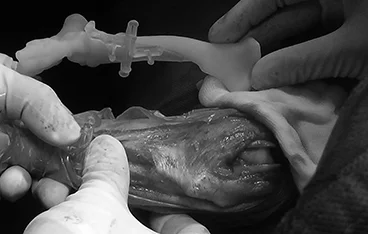

4. 천장골 탈구(SI luxation) 최소침습 수술

외상으로 인한 골반 비대칭 및 보행 장애를 최소 절개로 정복하여 회복 시간을 줄이고 통증을 최소화합니다.